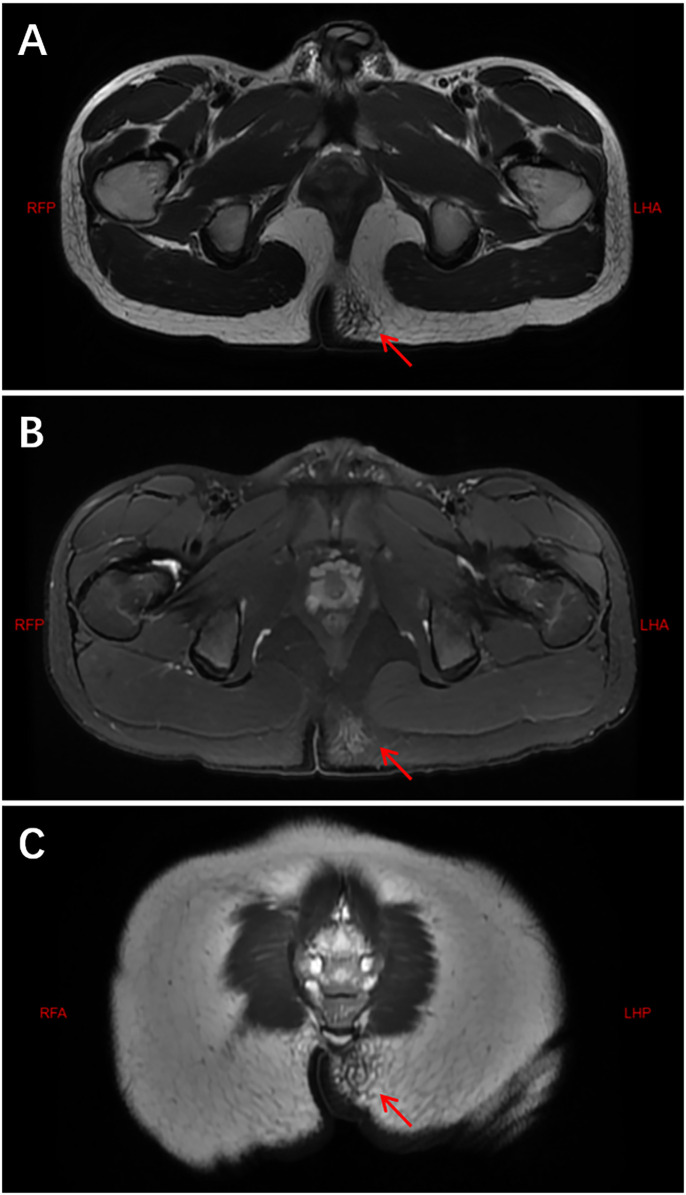

背景:炎性肌纤维母细胞瘤(IMT)是一种罕见的中间恶性潜能间充质肿瘤。虽然其临床病理特征已在成人中描述,但儿科人群的综合数据仍然有限。方法:回顾性分析2016年1月至2024年6月山西省儿童医院诊断为IMT的儿童患者。系统分析临床资料、影像学、组织病理学、免疫组化(IHC)和结果。结果:共纳入16例临床资料及随访资料完整的患者。男性10例,女性6例,中位年龄5.0岁。原发肿瘤部位及临床表现多样:8例位于腹腔及盆腔,表现为腹痛、恶心、呕吐、发热;4例位于头颈部及面部,3例表现为无痛性局部肿块,1例表现为吸气性呼吸困难;胸壁、臀区、左上肢各1例,均表现为无痛性局部肿块;肺部1例,表现为咳嗽、咳痰、反复呼吸道感染。所有16例患者均接受手术治疗;3例局部复发需要再次手术。最后随访中,15例无病,1例在alk靶向治疗下保持稳定。结论:儿童IMT是一种罕见的低级别恶性肿瘤,预后良好。完全手术切除仍然是治疗的基石。alk靶向治疗可使不可切除或复发性疾病的患者受益。由于有复发的危险,需要长期监测。

Results: A total of 16 patients with complete clinical data and follow-up information were included. There were 10 male and 6 female patients, with a median age of 5.0 years. The primary tumor locations and clinical manifestations were diverse: 8 cases were located in the abdominal and pelvic cavities, presenting with abdominal pain, nausea, vomiting, and fever; 4 cases were located in the head, neck, and facial region, with 3 presenting as painless localized masses and 1 with inspiratory dyspnea; 1 case each occurred in the chest wall, gluteal region, and left upper limb, all presenting with painless localized masses; and 1 case occurred in the lung, presenting with cough, sputum, and recurrent respiratory infections. All 16 patients underwent surgery; three developed local recurrence requiring re-operation. At last follow-up, 15 were disease-free and one remained stable on ALK-targeted therapy.